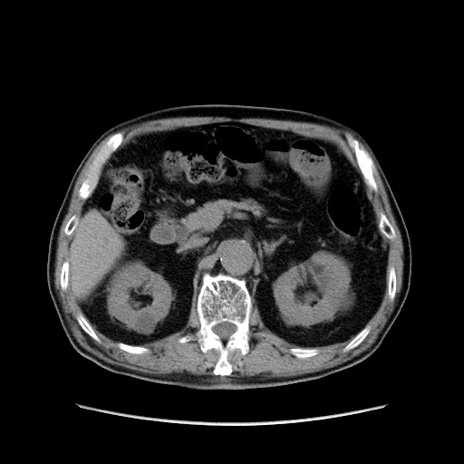

症例24(横断像)

【症例】80歳代男性

【主訴】左側腹部痛、嘔吐

【現病歴】本日早朝より左腹部に痛みあり。昼頃嘔吐認めたため、救急要請。

【既往歴】直腸癌(Mile手術)、胆摘

【身体所見】意識清明、BT 35.9℃、BP 221/93mmHg、SpO2 97%(RA) 、腹部:左ストーマ周囲に限局性の腹部膨隆あり。 膨隆部自発痛・圧痛あり・軟。

【データ】WBC 7700、CRP 0.09